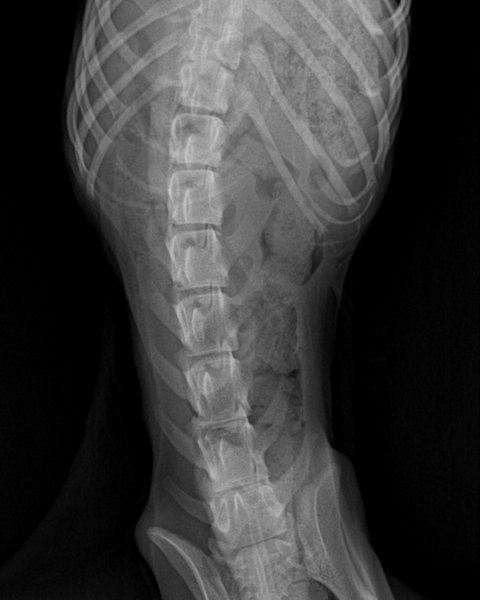

몸무게2.8키로/PSS(소간증)/예전홍역의심/골절수술부위2차감염/빈혈/탈수/저체중/저체온/눈궤양/암모니아,신장,칼슘,거의 모든수치 이상/이빨멜라닌색소소멸/위장음식물없음등을 알게됐습니다.

그리고 예전기록을 보여달라 요청해 보니 마루 간은 정상 사이즈였습니다.(3월9일 내원엑스레이)

선천성을 운운하던 pss소견은 애초에 선천성이 아니었다합니다.